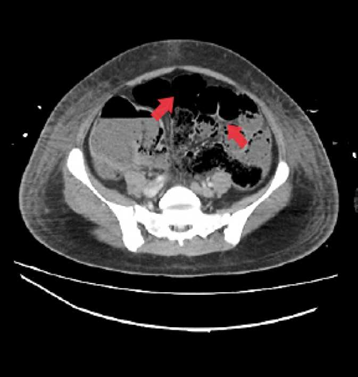

La NI tiene dos tipos de patrones en la radiografía: el quístico o en burbuja (benigno), típico de la neumatosis primaria cistoide, y el lineal o curvilíneo, que se relaciona en mayor proporción con isquemia y necrosis intestinal. En la Figura 4 se evidencia distensión generalizada de asas gruesas y delgadas asociada a la presencia de neumatosis intestinal; este hallazgo se encontró en la TAC abdominal total de una paciente del Hospital San Rafael Tunja diferente a la del caso presentado, ya que a esta última no se le realizó este examen antes de someterla a exploración quirúrgica.

Corte axial de tomografía axial computarizada de abdomen total que evidencia asas intestinales delgadas y gruesas con retardo en el tránsito del contraste asociada a la presencia de neumatosis intestinal y con compromiso de las paredes del íleon distal y ciego.

Figura 4: Corte axial de tomografía axial computarizada de abdomen total que evidencia asas intestinales delgadas y gruesas con retardo en el tránsito del contraste asociada a la presencia de neumatosis intestinal y con compromiso de las paredes del íleon distal y ciego.

Fuente: Documento obtenido durante la realización del estudio.